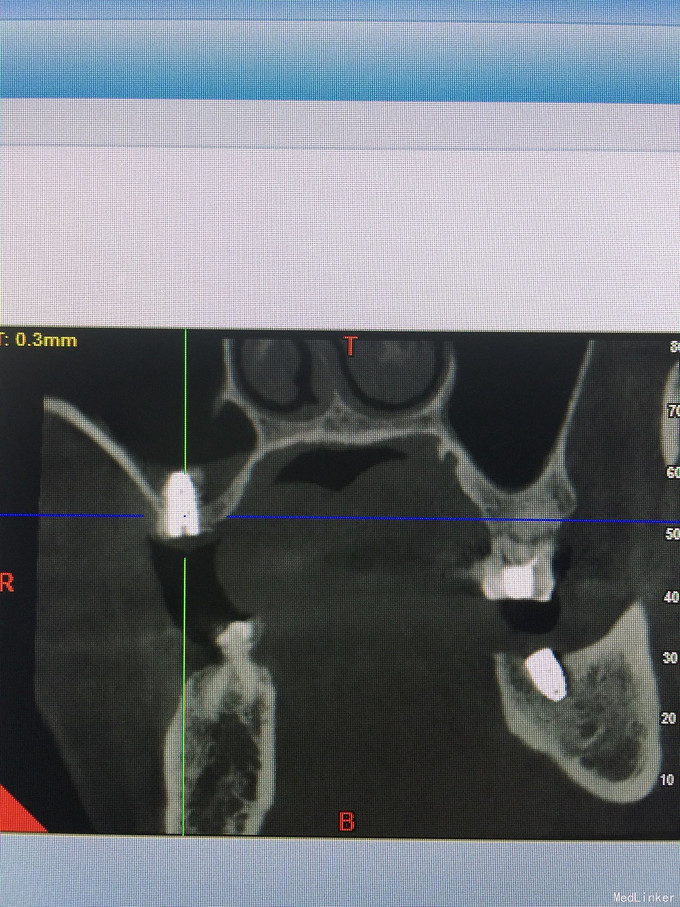

张先生,右上6缺失多年,要求种植

骨量只有2.4毫米

上颌窦内提,同期植入4.1-10植体